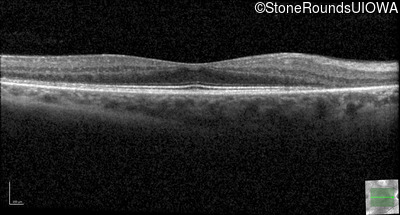

Optical Coherence Tomography - Right - 20/32

Exemplar / OCT Stack